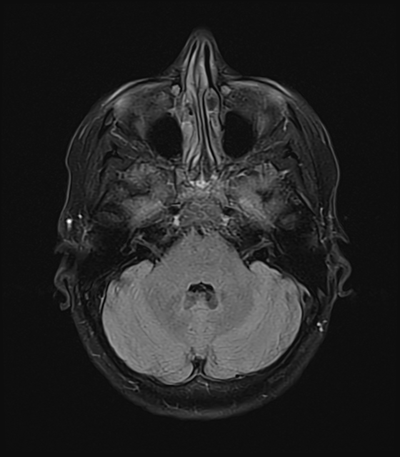

An 50 year-old man with lung adenoCA (known metastases to brain, spine, and adrenal glands) presents to the ED with worsening right arm and leg weakness. He had just gotten a routine MRI of his brain yesterday that re-demonstrated his known right occipital and left frontal metastases, though with an increase in vasogenic edema (mainly associated with the left frontal metastasis) as compared with prior. The ED consults you because of his abnormal MRI with worsening symptoms, and to inquire whether surgical intervention is acutely warranted.

MRI brain (FLAIR)